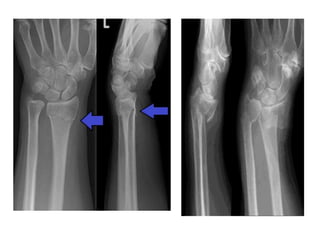

Galeazzi- (Counter part of Monteggia)

• Galeazzi- (Counter part

of Monteggia) fracture

of the lower third of the

radius with dislocation

or subluxation of the

distal radio-ulnar joint.

Colles Fracture

Colle’s fracture-

• Radius gets fractured about 2 cm above its lower end

due to fall on outstretched hand

Smith’s fracture- Reverse of Colle’s fracture

• If distal fragments gets displaced anteriorly

Colle’s fracture- • Radiusgets fractured about 2 cm above its lower end due to fall on outstretched hand Smith’s fracture- Reverse of Colle’s fracture • If distal fragments gets displaced anteriorly